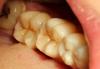

METT Опубликовано 27 марта, 2013 Автор Поделиться Опубликовано 27 марта, 2013 Фиксация вкладки на 16 1 Ссылка на комментарий

METT Опубликовано 27 марта, 2013 Автор Поделиться Опубликовано 27 марта, 2013 Пломбочка на 17 и покраска пломбы на 47 Ссылка на комментарий